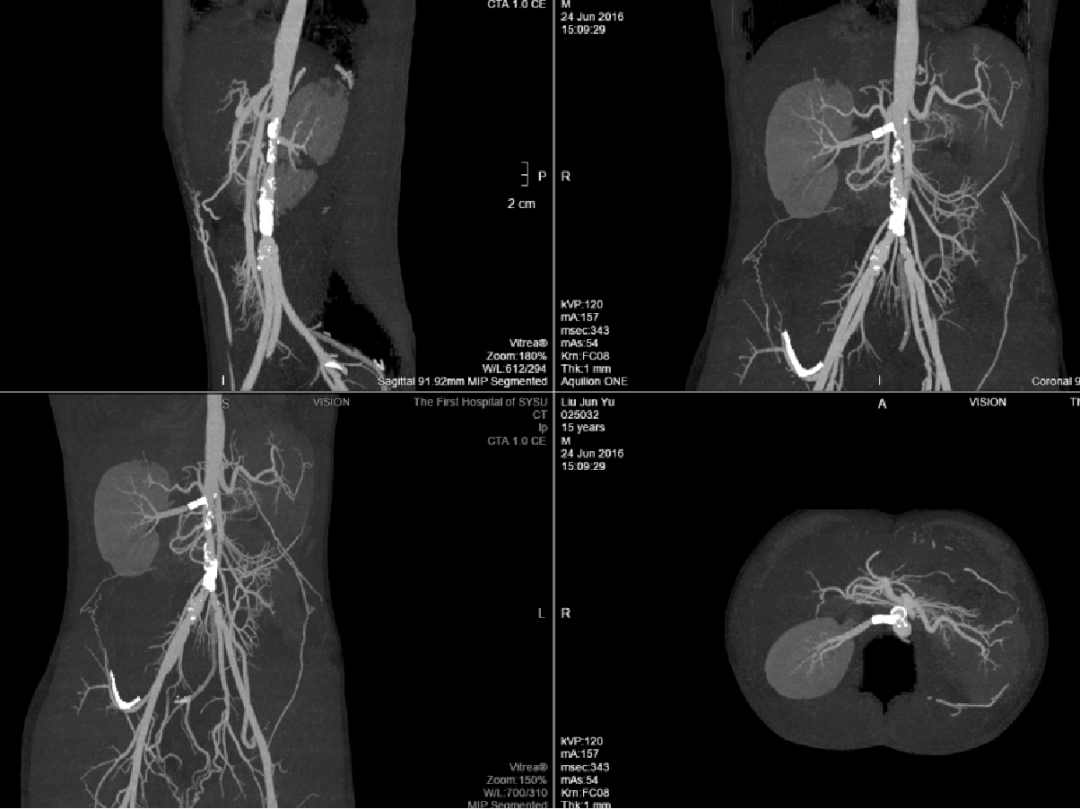

大动脉炎

男性,15岁

发现血压增高五年,双下肢乏力伴麻木一年余

最高血压达180/110mmHg。四年前行右肾动脉支架成形术,一年前复查时发现再狭窄,我院超声、CTA等相关检查提示“多发性大动脉炎”。

大动脉炎,主动脉及其主要分支广泛受累,多发节段性狭窄

右侧肾动脉近段支架置入,支架内腔稍变窄,右肾灌注尚可显影良好

左肾萎缩

手术方案:

腹主动脉-双侧髂动脉人工血管旁路术+右肾自体移植术

右肾移植于右髂窝,肾动脉与右髂内动脉吻合

术后5天复查CT

术后1年

术后3年